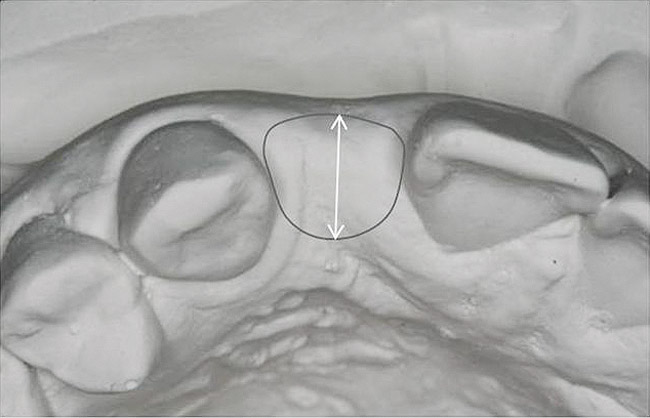

Figure 13   Exploiting study casts for planning single-tooth implant placement and restoration: Mounted study casts permit an estimation of available bone volume (Fig 13); measure the bound edentulous space inter-tooth dimensions (Fig 14); measure the available inter-arch dimension (restorative space) (Fig 15); and evaluate alveolar ridge/tooth relationships (distance from zenith represented by plastic stent to ridge crest) (Fig 16).

Figure 13

Figure 14   Exploiting study casts for planning single-tooth implant placement and restoration: Mounted study casts permit an estimation of available bone volume (Fig 13); measure the bound edentulous space inter-tooth dimensions (Fig 14); measure the available inter-arch dimension (restorative space) (Fig 15); and evaluate alveolar ridge/tooth relationships (distance from zenith represented by plastic stent to ridge crest) (Fig 16).

Figure 14

The exploration of this architecture is only fully achieved by evaluation of study casts that clearly reveal the detailed anatomy of the alveolus and the peri-coronal tissues. Study casts should be mounted in maximum intercuspal position for the complete treatment planning of single-tooth dental implants. Mounted casts enable estimation of the required 6 mm of space between the ridge crest (approximately 2 mm submucosal) and the opposing tooth and measurement of the mesiodistal interdental distance. The orientation of the implant in the alveolus should neither interfere with the required occlusion nor should it obviate the placement of an esthetic crown (eg, excessively buccal orientation). This can be revealed through the diagnostic waxing process. Encroachment of opposing teeth into the bound edentulous space may suggest the need for possible adjustment or orthodontic movement of the antagonist. When excellent study casts are mounted, it is possible to: estimate bone volume; measure bound edentulous space inter-tooth dimensions; measure inter-arch dimensions; and evaluate alveolar ridge/tooth relationships (superseding resorbed ridge classification) (Figure 13 through Figure 16).